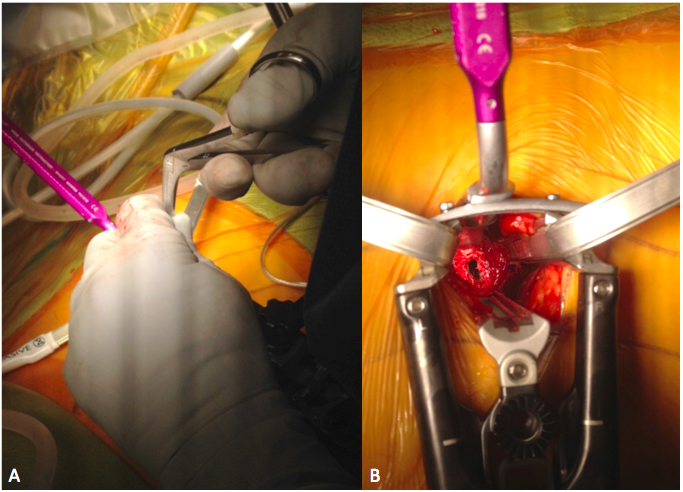

6. Berjano P, Gautschi OP, Schils F, Tessitore E. Extreme lateral interbody fusion (XLIF®): how I do it. Acta Neurochir (Wien) 2015;157(3):547-51. doi: 10.1007/s00701-014-2248-9

19. Guerin P, Obeid I, Bourghli A, Masquefa T, Luc S, Gille O, et al. The lumbosacral plexus: anatomic considerations for minimally inva- sive retroperitoneal transpsoas approach. Surg Radiol Anat 2012;34(2):151-7. doi: 10.1007/s00276-011-0881-z

36. Moller DJ, Slimack NP, Acosta FL Jr, Koski TR, Fessler RG, Liu JC. Minimally invasive lateral lumbar interbody fusion and transpsoas approach-related morbidity. Neurosurg Focus 2011;31(4):E4. doi: 10.3171/2011.7.FOCUS11137